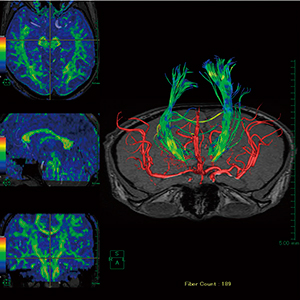

図4 拡散テンソル解析

さまざまな情報を付加して表示することが可能。

独自アルゴリズムによる当社の拡散テンソル解析は,高速演算によってリアルタイムにマウス上の指定点からファイバーを描画することが可能である。本機能は,センサーとのナビゲーション機能をイメージして搭載されており,脳外科医が実際に推定したい部分を瞬時に表示することができる。また,推定されたファイバーは,さまざまなモダリティの画像と組み合わせることが可能であり,血管構造や椎体などと組み合わせて表示することで,神経走行の理解を深めることが可能である(図4)。また,当社のソフトウェアは,あらゆるモダリティメーカーのデータに対応しており,さらに撮影される身体部位を限定していないため,施設によっては手根骨付近や腰椎馬尾神経など,さまざまな領域で実施されているケースもある。